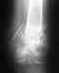

дравствуйте! У меня такая проблема. Упал, катаясь на велосипеде, заработал себе вывих ключицы (акромиального соединения).

Сначала по рентгену сказали: ушиб, сейчас оказалось, что вывих. Предложили два варианта операции: по старой методике, с наложением гипса (цена — около 5000 р) и с применением специальной пластины от Synthes (цена — 42000 за пластину). Можете подсказать преимущества и недостатки этих вариантов, и отражают ли эти цены действительность?